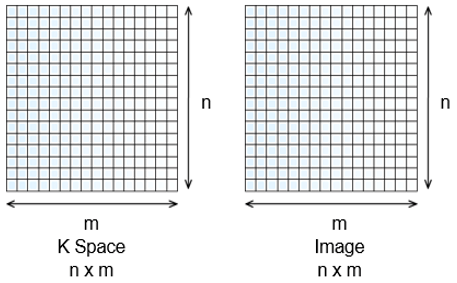

Dimensions of the K Space

The dimensions of the Fourier space and the image are the same. This means that the size of the field and the size of the matrix we set in the scanner parameters are in fact the size of the FOV and the matrix of the Fourier space. It is the acquisition matrix. In reality, the image is reworked before restitution or reconstruction. In general, the image restored is a 5122 image. The size of the matrix represents the number of pixels or the number of tiny squares inside the large square. On a 512 matrix, there will be 512 rows of pixels and 512 columns of pixels.

Pixels of the K Space

Each pixel of the Fourier space codes for all pixels of the image. In other words, in each of the pixels of the K space, we will have information on all the pixels of the image.

Pixels of the Image

Each pixel of the image has been coded by all the pixels of the K space. In other words, each of the pixels of the image has received information from the entire K space.